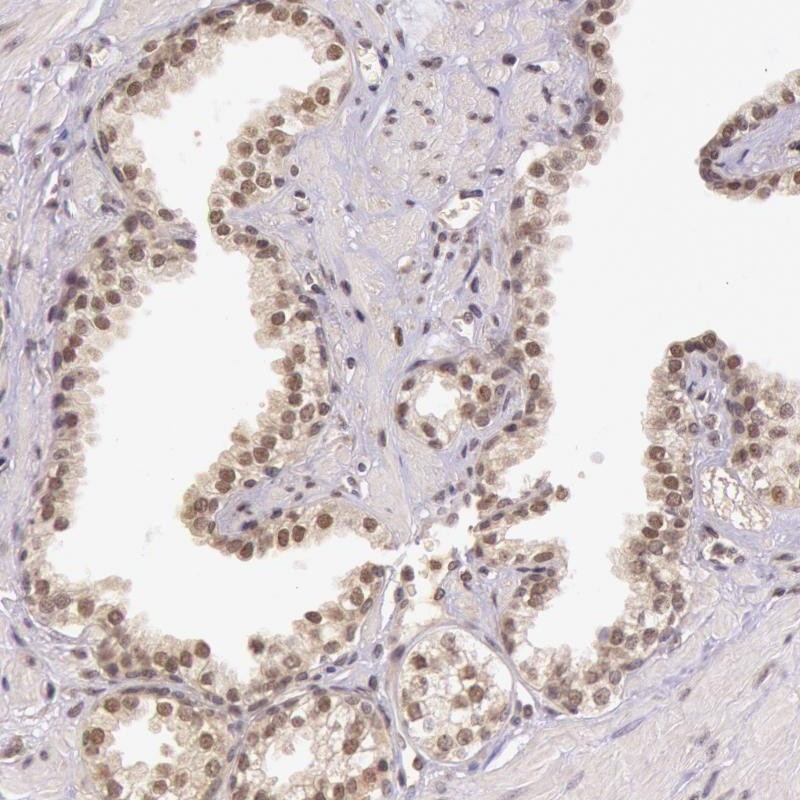

Immunohistochemical staining of human prostate shows nuclear positivity in glandular cells.